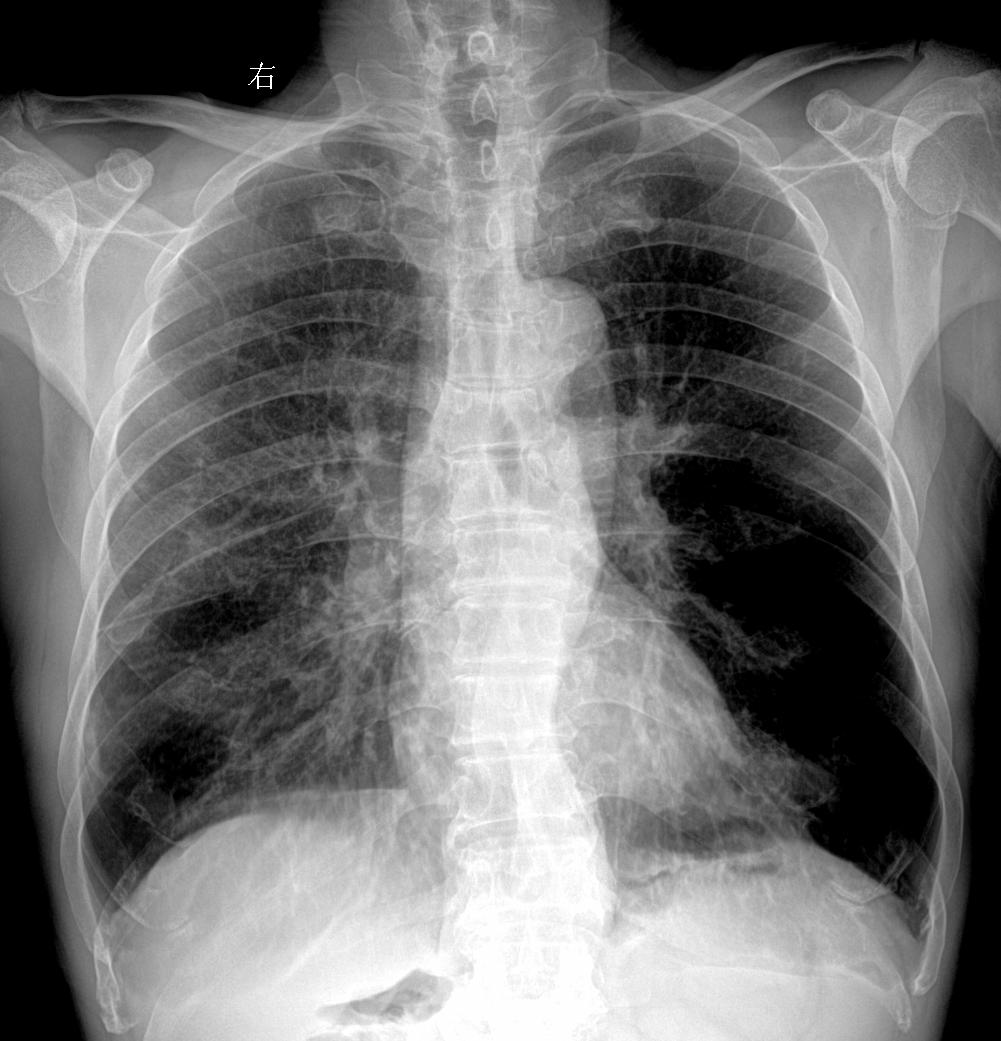

回归工作 双肺可见高密度影钙化灶?陈旧性肺结核?主诉:女 68y 胸闷...